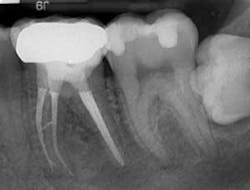

Fig. 2. Distal view showing mid-root isthmus canal and apical bifurcation of the MB canal filled.

Obturation was accomplished with the continuous wave obturation technique. Final radiographs revealed mesial canals with severe curvatures filled with no evidence of apical transportation with an isthmus canal as large as a primary canal cleaned and filled, and an apical bifurcation of the MB canal. The distal canals were apically confluent, and obturated with remarkable accuracy considering the large apical canal diameters.